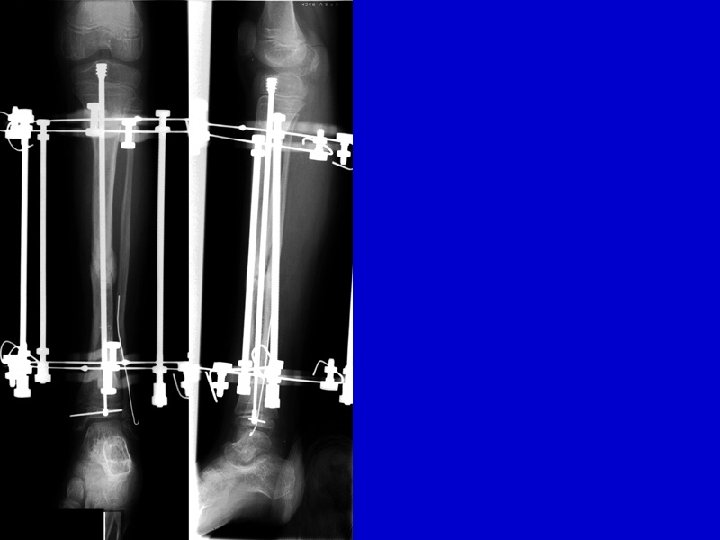

Type II Treatment Bone transport Acute shortening

CPT resection

acute shortening re-lengthening

bone transport healed

Re. Fx IM rod follow-up